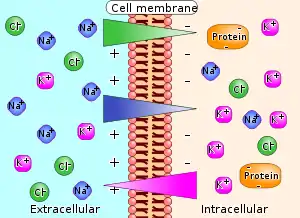

| Diagram of ion concentrations and charge across a semi-permeable cellular membrane. | |

Calcium, magnesium, potassium, and sodium ions are cations (+), while chloride, and phosphate ions are anions (−).

General function

Electrolytes are important because they are what cells (especially nerve, heart and muscle cells) use to maintain voltages across their cell membranes. Electrolytes have different functions, and an important one is to carry electrical impulses between cells. Kidneys work to keep the electrolyte concentrations in blood constant despite changes in the body.[5][7] For example, during heavy exercise, electrolytes are lost in sweat, particularly in the form of sodium and potassium.[7] The kidneys can also generate dilute urine to balance sodium levels.[7] These electrolytes must be replaced to keep the electrolyte concentrations of the body fluids constant. Hyponatremia, or low sodium, is the most commonly seen type of electrolyte imbalance.[8][9]